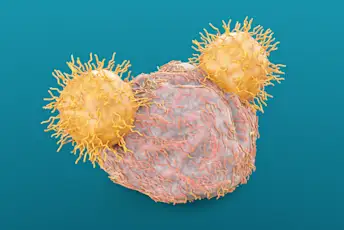

了解你的T细胞

你可能认不出这些增强的抗癌白细胞。这是你的re-introduction。